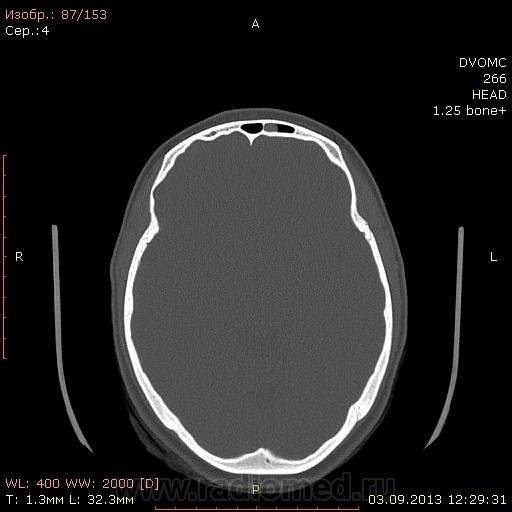

КТ головного мозга. Выстрел в лоб. В упор.

Дувушка 19 лет. В направлении огнестрельное ранение лобной области(пневматический пистолет). Металлический шарик вытащили из под кожи. Отправили на КТ и наблюдение в поликлинику. Из жалоб небольшое головокружение, головная боль. DICOM здесь http://files.mail.ru/F25AE2CF07AB4813BF046CE33FB20034

Кости вроде целы, мозги тоже ничего?

Этмоидит слева (передние решетки), утолщение слизистой в левой в/ч пазухе. И полип верхней стенки левой лобной пазухи. Это не кровь, плотность 110 ед.Н и выше при большом увеличении. По дайкомам травматических изменений нет.